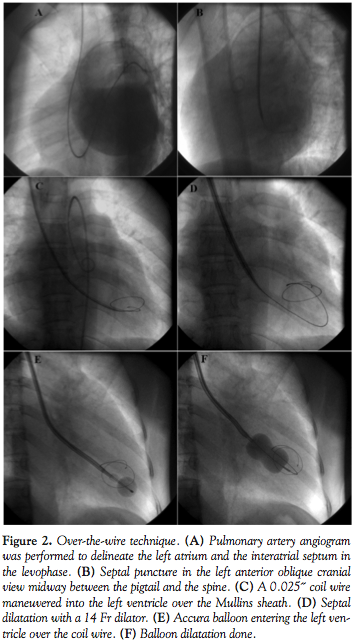

LA opacification. Through the 8 Fr venous sheath, an NIH catheter (Cordis Corporation) was guided into the pulmonary artery. A pulmonary artery angiogram was done in the left anterior oblique (LAO) projection to delineate the interatrial septum (IAS) in the levophase.

Septal puncture. A pediatric 6 Fr Mullins sheath (Medtronic) was advanced over a 0.032˝ wire, and through it a 21 G pediatric Brokenborough needle (Medtronic) with a manually modified acute angled tip was advanced (Figure 1). During puncture, the direction indicator of the needle must point in the 7-8 o’clock position, as opposed to the conventional 5 o’clock position. The IAS was punctured in the LAO view using the pigtail as guide. The IAS puncture was done below the lower extent of the pigtail midway between the pigtail and the spine (see Video 1 at invasivecardiology.com). The entry into the left atrium was confirmed and left atrial pressure was measured. Following septal puncture, 3000 IU of heparin was given.

Over–the-wire technique. In case 1, after septal puncture, a 0.025˝ coiled tip wire (Vascular Concepts) was passed through the Mullins sheath in such a manner as to directly enter the left ventricle. The IAS was then dilated using a 14 Fr septal dilator and an appropriately sized Accura balloon (Vascular Concepts) was advanced into the left ventricle over the coil wire (Figure 2).